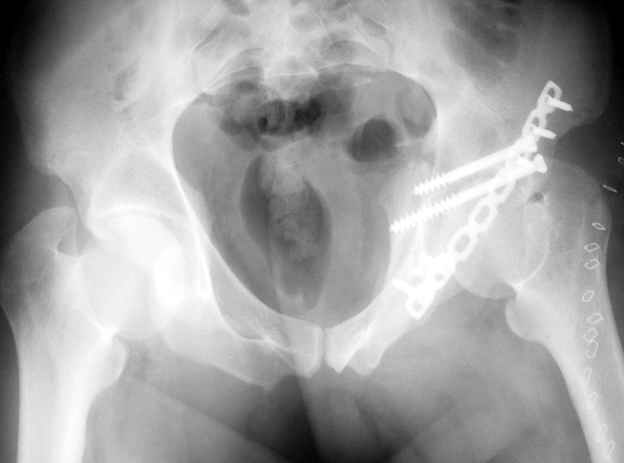

Уважаемые коллеги,Мужчина 36 лет от роду попал в ДТП 24.08.04 Рентгенограммы в приложении.

Диагноз- перелом с вовлечением таза, разрыв правого сакро-илиак сочленения vertical shear injury, перелом крыла подвздошной кости?, перелом ацетабулум Т type или Both column?, перелом шейки бедра, перелом проксимального отдела бедра.

перелом крыла правой подвздошной кости, перелом обеих колонн вертлужной впадины, двусторонний перелом лонных костей (С2.2) повреждение передних связок правого крестцово-подвздошного сочленения,

ипсилатеральный перелом шейки и диафиза бедра.

Не дождавшись советов, в понедельник прооперировал больного, заняло времени..., но все сделал в один этап: сначала фиксировал ипсилатеральный перелом бедра и шейки реконструктивным гвоздем Smith&Nephews, потом из расширенного илеофеморального доступа фиксировал перелом крыла подвздошной кости тягловым винтом, нейтрализующей пластиной заднюю колонну, и тягловыми винтами 3,5 мм переднюю колонну.

шейку (благо перелом шейки 2 типа -относительно стабильный) затем фрагмент крыла подвздошной кости Lag screw, далее пластина на заднюю колонну и винты в переднюю колонну.(с размерами и направлением винтов ошибка вышла:-((, но интраоперационно у меня была полная уверенность , что винты *ушли* в лонную кость).